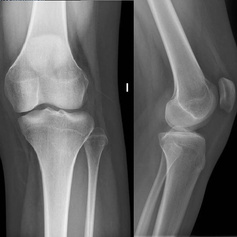

Protesis

Cadera y rodilla

Cirugía especializada para reemplazo articular en situaciones de desgaste avanzado.